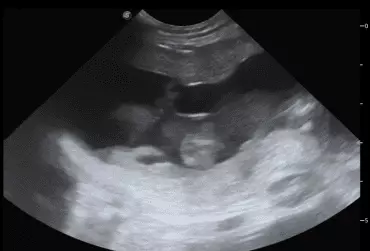

W literaturze opisano niewiele przypadków ciąż bliźniaczych jednokosmówkowych u suk. W trakcie wczesnej diagnostyki ultrasonograficznej ciąży u suki rasy whippet (chart angielski) zobrazowano pęcherz ciążowy, w którym znajdowały się dwa zarodki. Podczas badań kontrol­nych zarodki, a później płody wykazywały prawidłową organogenezę i żywotność. Ich rozwój przebiegał podobnie względem pozostałych ośmiu płodów. W 63. dniu ciąży wykonano zabieg cesarskiego cięcia i wydobyto dwa płody tej samej płci, o bardzo podobnym wyglądzie, z dwóch pęcherzy płodowych przyczepionych do jednego łożyska, oraz pozostałe osiem płodów.

Ryzyko związane z ciążą bliźniaczą jednokosmówkową u ciężarnych suk nadal jest nieznane, istnieją jednak doniesienia o śmierci płodu lub płodów w ciążach jednokosmówkowych u tego gatunku. Badanie ultrasonograficzne w czasie ciąży pozwala na wczesne rozpoznanie ciąży jednokosmówkowej, a monitorowanie żywotności płodów może ograniczyć ryzyko powikłań położniczych i przynieść korzyści zdrowotne zarówno samicy, jak i rodzeństwu z miotu.